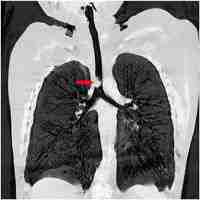

| Abstract | Background Allergic rhinitis is the most common allergic disease encountered in a primary care setting. Diagnosis is often made clinically based on response to empiric therapy. However, with long-term treatment failure and/or atypical disease presentation, a differential diagnosis should be considered. The following is a report of an unusual and rare presentation of a subglottic tracheal angiomyomatous hamartoma in an adolescent, treated for many years as allergic rhinoconjunctivitis and asthma. Case presentation A 12-year-old Caucasian was referred to the allergy clinic with a lifetime history of bronchospasms and rhinoconjunctivitis symptoms, treated for many years for asthma and environmental allergies. Cough, posterior nasal drainage, self-described “choking on phlegm,” and a sensation of “a flap in the throat,”, worsened 5 months prior to the initial evaluation. Puncture skin testing for common environmental allergens was negative. Spirometry, performed due to history of chronic cough, showed blunting of the forced expiratory phase. A chest X-ray, immediately ordered to rule out possible extrapulmonary obstruction, showed bilateral bibasilar infiltrates. A noncontrast computerized tomographic scan of the chest, ordered to further elucidate X-ray findings, revealed a subglottic tracheal mass. Following a subsequent transfer and admission to a tertiary hospital center, microlaryngoscopy, bronchoscopy, and microsuspension laryngoscopy were performed to remove the tracheal mass. Pathology confirmed squamous mucosa with polypoid angiomyomatous changes and chronic inflammatory features consistent with angiomyomatous hamartoma. Surgical intervention was successful, and follow-up 1 year postoperatively revealed a healthy, asymptomatic adolescent child with normal lung function. Conclusions Although posterior nasal drainage and cough are typical presenting symptoms in the general patient population, they may be clinically impactful as they could disguise more serious medical conditions. A detailed history and careful physical examination may provide a high index of suspicion of disease, and can help work the differential diagnosis. This case presentation is the first documentation of subglottic hamartoma reported in the pediatric literature with clinical manifestation of environmental allergy and asthma symptoms. |